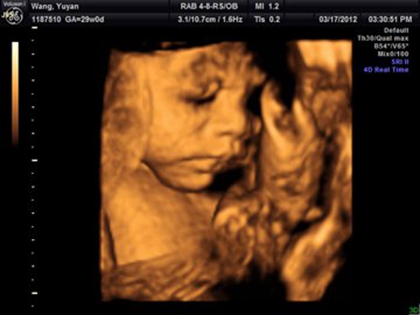

网上流传着四维彩超的报告上如果是有三条线就是女孩,而如果没有三条就是男孩,那么四维女宝宝三条线特征图片长什么样呢,四维男宝也有三条线吗?更多关于生男生女的相关内容尽在孕宝网。

四维女宝宝三条线特征图片长什么样?

其实网上流传着的这种说法并没有依据,原因是网上说的三条线是指女孩生殖器上的线,但是四维彩超上面一般医生是不会显示出完整的生殖器的,还有就是,四维彩超的三条线是无法看出男女性别的,这三条线代表的是脊柱线,还有就是通过三条线来看男女性别的方式误差也是比较大的。

四维彩超其实是实时的三维,是有一个立体成像的过程,因为胎儿是团抱式的,胎儿一部分会被遮挡,所以四维应该会更准确一些,但是不是绝对的。实际在B超进行胎儿性别鉴定时,有可能男孩生殖器被遮挡导致误认为是女孩,因此还是要找专业的医生来看才能下结论。